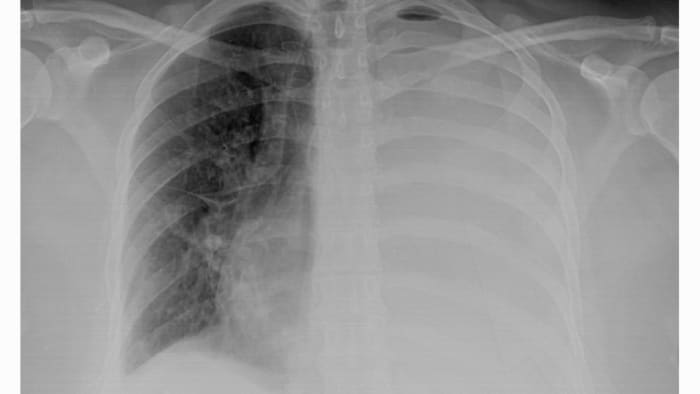

A local pediatrician in Belleville, Michigan, is clarifying that "white lung syndrome" is just another term for pneumonia, which is common during this time of year. The term does not refer to a new strain or infection. A 6-year-old boy in Belleville recently experienced a severe case of bacterial pneumonia, and his mother discovered the term while searching for answers online. The boy was eventually diagnosed and treated in the hospital. The CDC states that pneumonia cases are consistent with pre-pandemic levels, with occasional clusters. The pediatrician advises parents to advocate for their children and seek medical attention if symptoms such as coughing, trouble breathing, and fever persist.